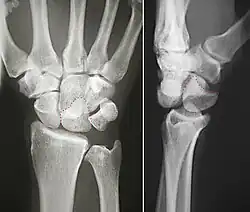

The left lunate bone

The proximal surface of the lunate bone is smooth and convex, articulating with the radius. The lateral surface is flat and narrow, with a crescentic facet for articulation with the scaphoid bone. The medial surface possesses a smooth and quadrilateral facet for articulation with the triquetral bone. The palmar surface is rough, as is the dorsal surface. The dorsal surface is broad and rounded. The distal surface of the bone is deep and concave.[4]